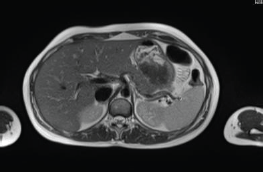

The patient continued treatment with trastuzumab and docetaxel for eight cycles. Whole-body nuclear magnetic resonance without contrast after chemotherapy ended found: Breast lesion reduced by more than 50% and the size and functionality of the hepatic lesion reduced. The patient continued treatment with trastuzumab + pertuzumab, Decapeptyl and exemestane. Whole-body nuclear magnetic resonance 1 year later found: complete remission of hepatic (Figure 2) and bone lesions. Breast ultrasound found two millimetric formations measuring 10 and 7 mm in the upper outer quadrant of the right Breast.

Figure 2. Whole-body nuclear magnetic resonance without contrast: complete remission of the hepatic lesion.